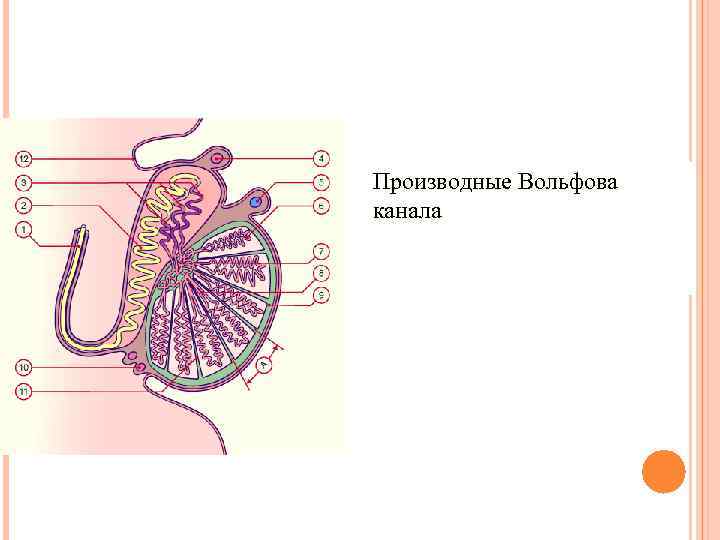

Производные Вольфова канала

Производные Вольфова канала